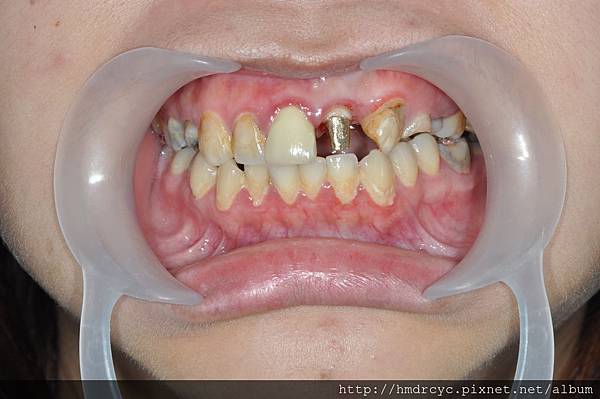

橋頭的K小姐有相同問題門牙斷裂

經過X光評估建議先裝鑄心恢復

高雄欣美牙醫先幫忙把根管治療完成

裝上鑄心後牙齒的高度寬度都恢復

根管治療完成先裝鑄心恢復

裝上鑄心